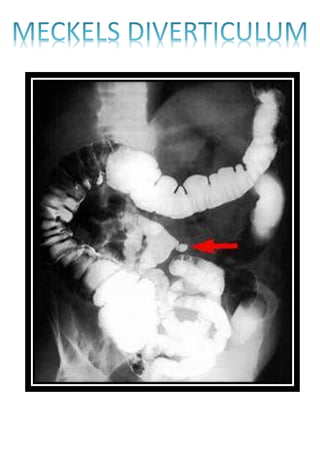

INTUSSUSCEPTION

CRAWFOOT APPEARANCE

CONTRAST STUDY